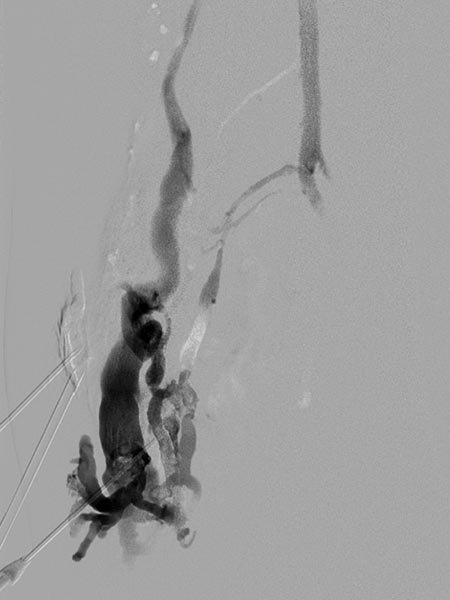

Digitale Subtraktionsangiographie nach Direktpunktion der venösen Malformation während der Sklerosierungsbehandlung. Neben der VM selbst zeigen sich direkte Kommunikationsvenen mit dem tiefen Leitvenensystem. Diese werden mittels Direktpunktion verschlossen mit viskösem Alkohol-Gel.

Röntgendurchleuchtung nach Direktpunktion der venösen Malformation während der Sklerosierungsbehandlung. Durch den Verschluss der Kommunikationsvenen mit dem tiefen Leitvenensystem ist die VM jetzt alleingestellt und kann sklerosiert werden. Nach Anspritzen kein Abstrom des Kontrastmittels mehr in die Leitvenen.